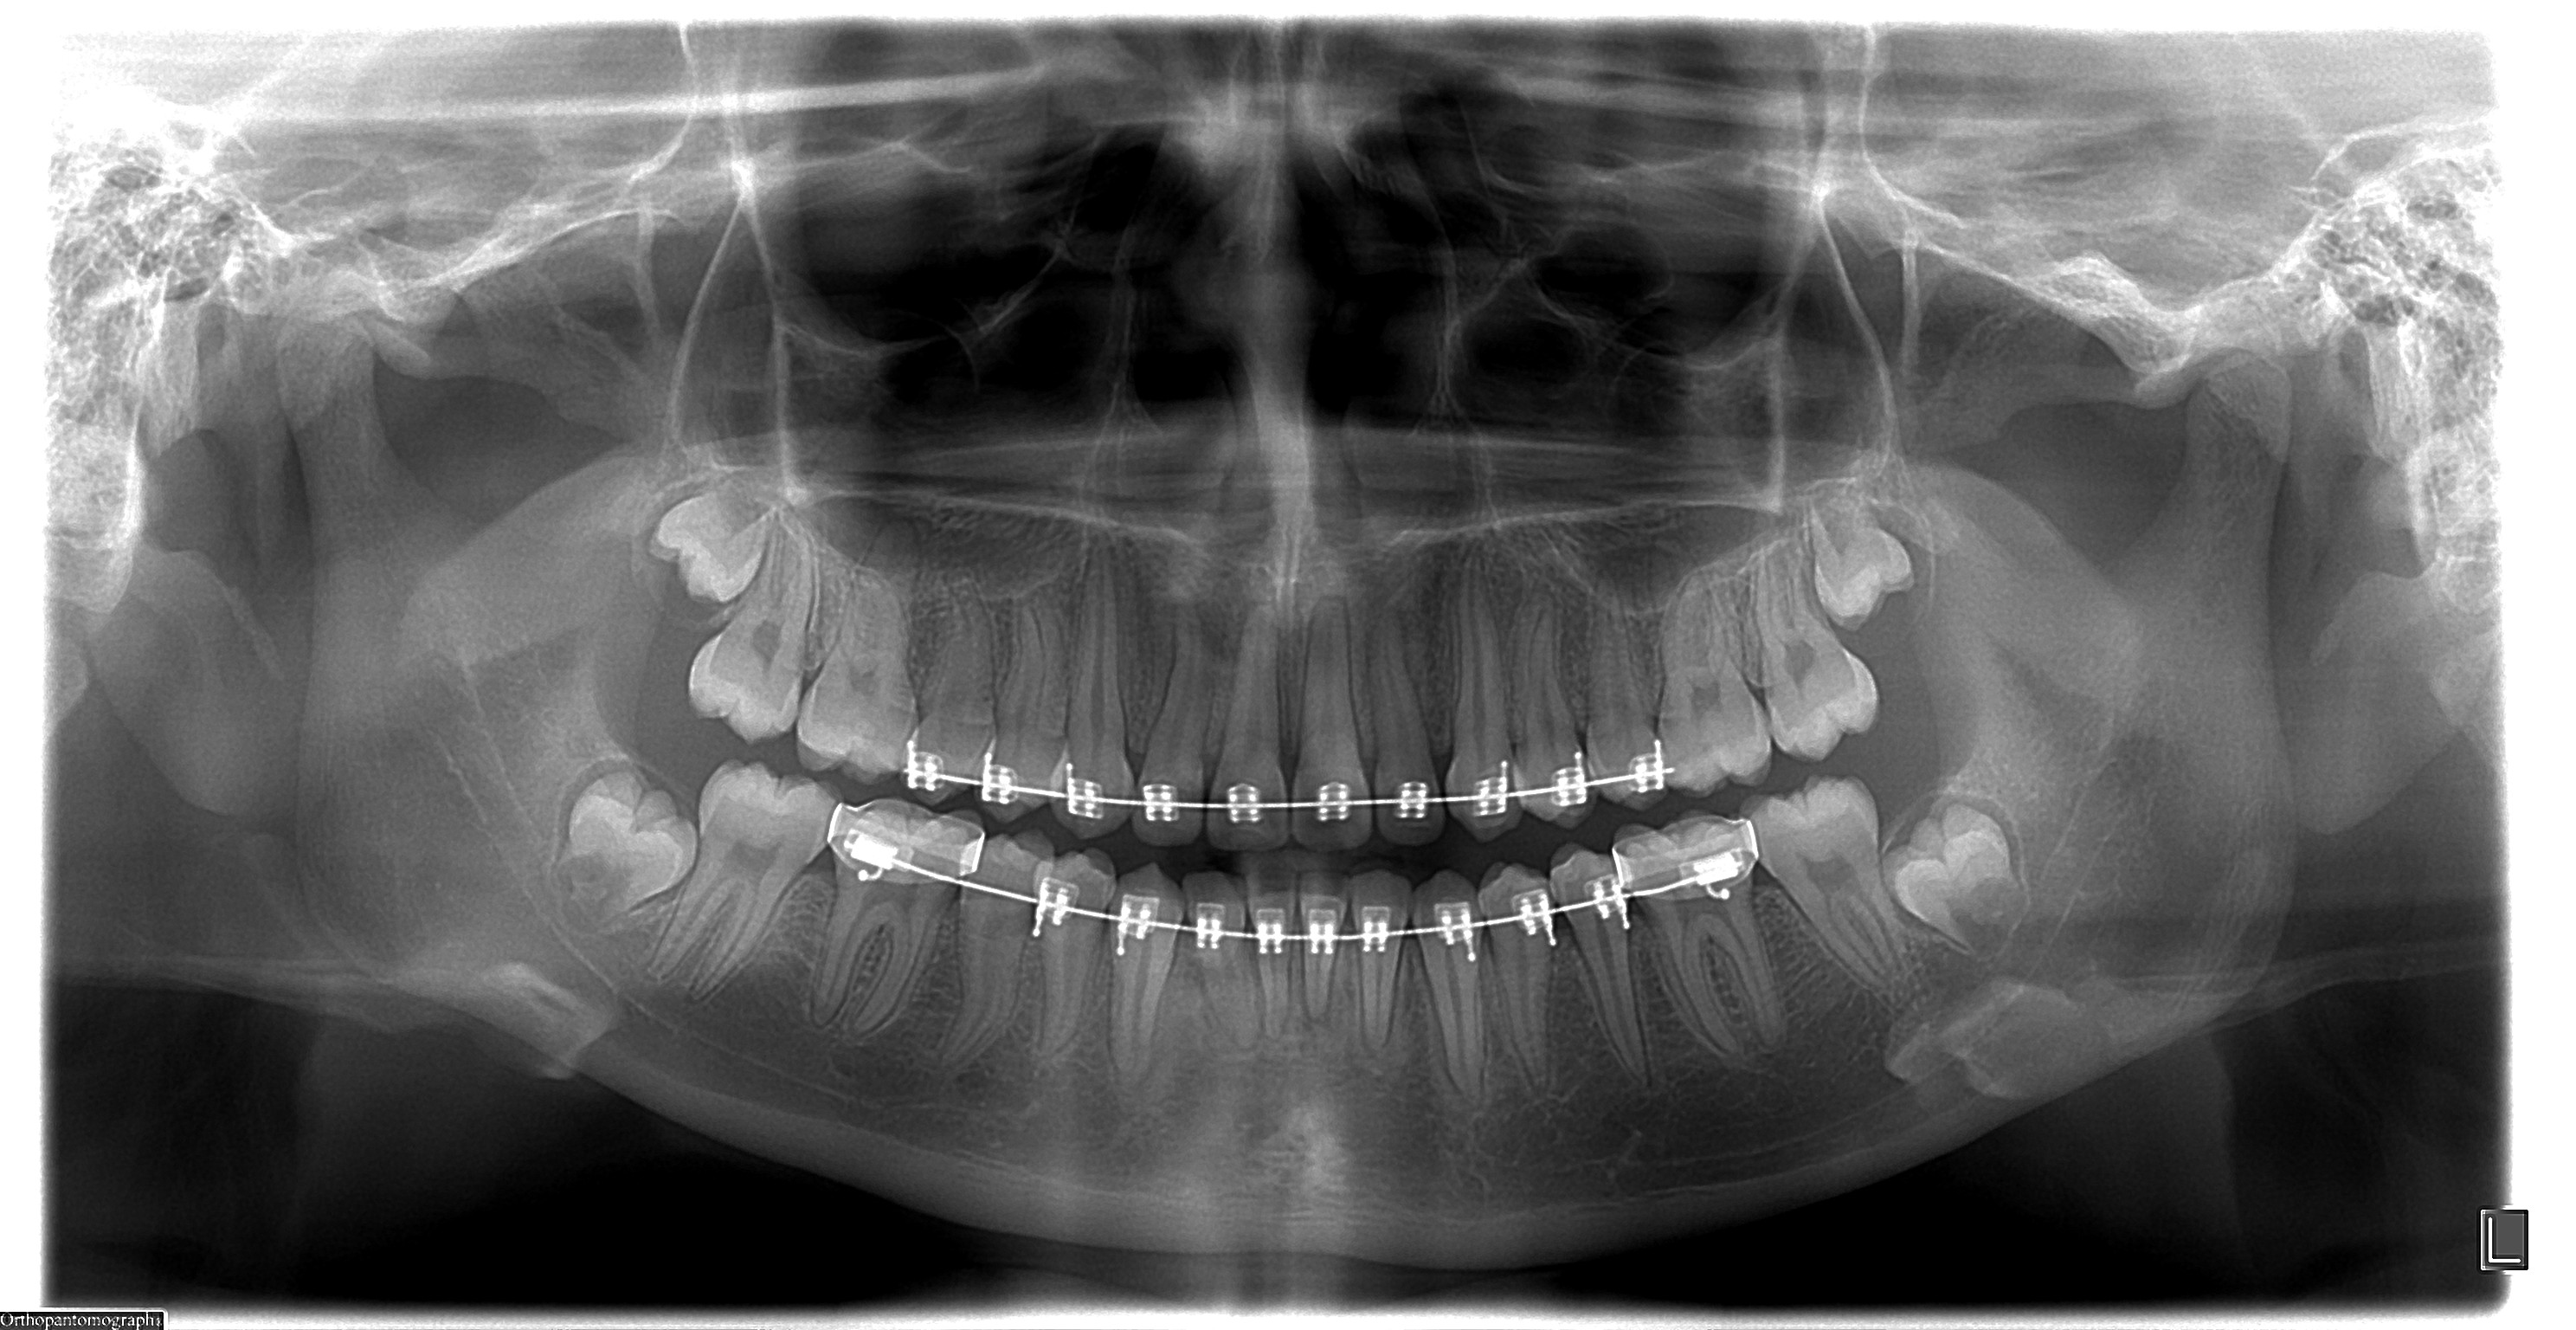

Debido a que trabajamos con la más avanzada tecnologia todas las radiografias digitales pueden ser entregadas/enviadas: Impresas en peliculas radiográficas con formato médico de alto contraste, CD y/o correo electrónico.